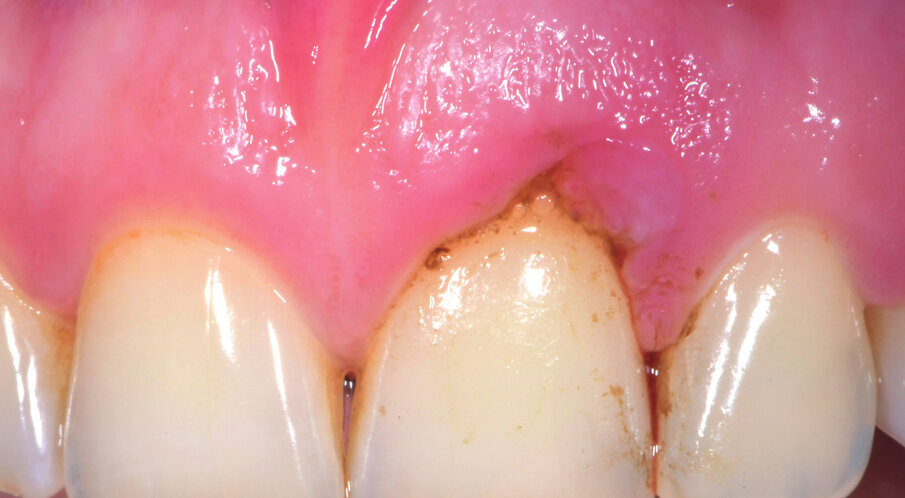

Il paziente di anni 33 viene inviato per trattamento di un gonfiore gengivale apparso circa 1 mese prima. È stato trattato con scaling e root planing senza ottenere il risultato voluto. All’esame obiettivo presenta una lieve gengivite interprossimale con infiammazione e gonfiore limitato alla parte vestibolare di 2.1 con sondaggio di 5 mm vestibolare e 7 mm disto-vestibolare (Fig. 1). La superficie della radice era stata strumentata una settimana prima e si presenta senza residui di tartaro e senza riassorbimenti esterni. Viene scelta l’applicazione di Ozosan Gel per ridurre subito i sintomi che limitavano la capacità del paziente di applicare una corretta igiene orale e per la sua azione antibatterica ma anche stimolante la guarigione. Ozosan Gel viene applicato per 8 minuti - azione anti batterica - seguito da lavaggio con fisiologica. Da subito il paziente segnala riduzione del dolore e viene istruito a uno spazzolamento delicato a roll con spazzolino morbido. Viene rivisto dopo 2 giorni ed effettuata una nuova applicazione di ozono. Controllo a 5 gg (Fig. 2), e applicazione di Ozosan Gel per due minuti per stimolare la guarigione (Fig. 3). Controllo a 2 sett. (Fig. 4) dove si nota recessione dei tessuti che erano stati strumentati in modo aggressivo. Guarigione a due mesi dove i tessuti stanno ricoprendo la recessione (Fig. 5).

Fig. 2 - Guarigione a 5 gg. Tessuti ancora edemetosi. Viene fatta una terza applicazione di ozosan per 2 minuti.

Fig. 3 - Applicazione di Ozosan per 2 min.